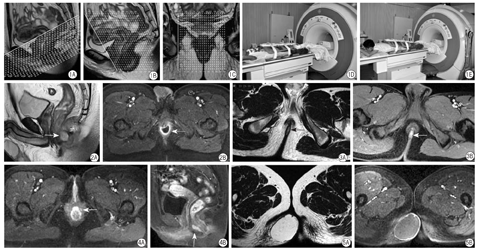

体位:(1)仰卧位:患者采取仰卧位时,足先进,身体左右居中,两手合抱置于前胸壁。束紧前后片线圈压迫小腹,可减轻呼吸运动的影响。如果病灶侵犯范围较大,可以考虑使用大范围扫描方案,扫描范围务必要将整个病灶覆盖。(2)俯卧位或折刀位:适用于骶尾部炎症病灶明显,患者因触痛难于仰卧时(图1)。

中心线:线圈中心对准耻骨联合,一般以正中冠状面及矢状面作为正中线,扫描时三平面定位图像上观察肛管不能偏上也不能偏下,确保肛管位于线圈的中心,定位线分别要垂直或平行于肛管正中轴线(图1)。

线圈:最常用的为多通道表面相控阵线圈,直肠肛管腔内线圈显示肛管解剖结构更优,但是由于自身的局限性,其在国内并没有得到广泛应用。